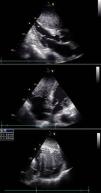

Transthoracic echocardiography revealed a large echogenic mass (66mm×60mm), involving the ventricular septum and protruding anteriorly and to the right (Fig. 2). Biventricular systolic function and inflow pattern were normal.

Two-dimensional transthoracic echocardiogram (top: parasternal long-axis view; middle: apical four-chamber view; bottom: subcostal view) showing involvement of the ventricular septum by the mass, which also protrudes into the right ventricular chamber. Maximum dimensions of 60mm×66mm assessed in subcostal view.